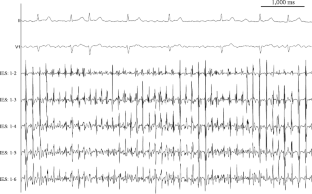

Bipolar electrograms were recorded via an octapolar catheter (2-mm electrode spacing) from left atrial CFAEs sites in 17 atrial fibrillation patients. The CFE-mean was calculated at IES of the electrode pairs 1–2, 1–3, 1–4, 1–5, and 1–6. The DF, regularity index (RI), and organization index (OI) were simultaneously analyzed.

Fig. 1

Fig. 2

Fig. 3